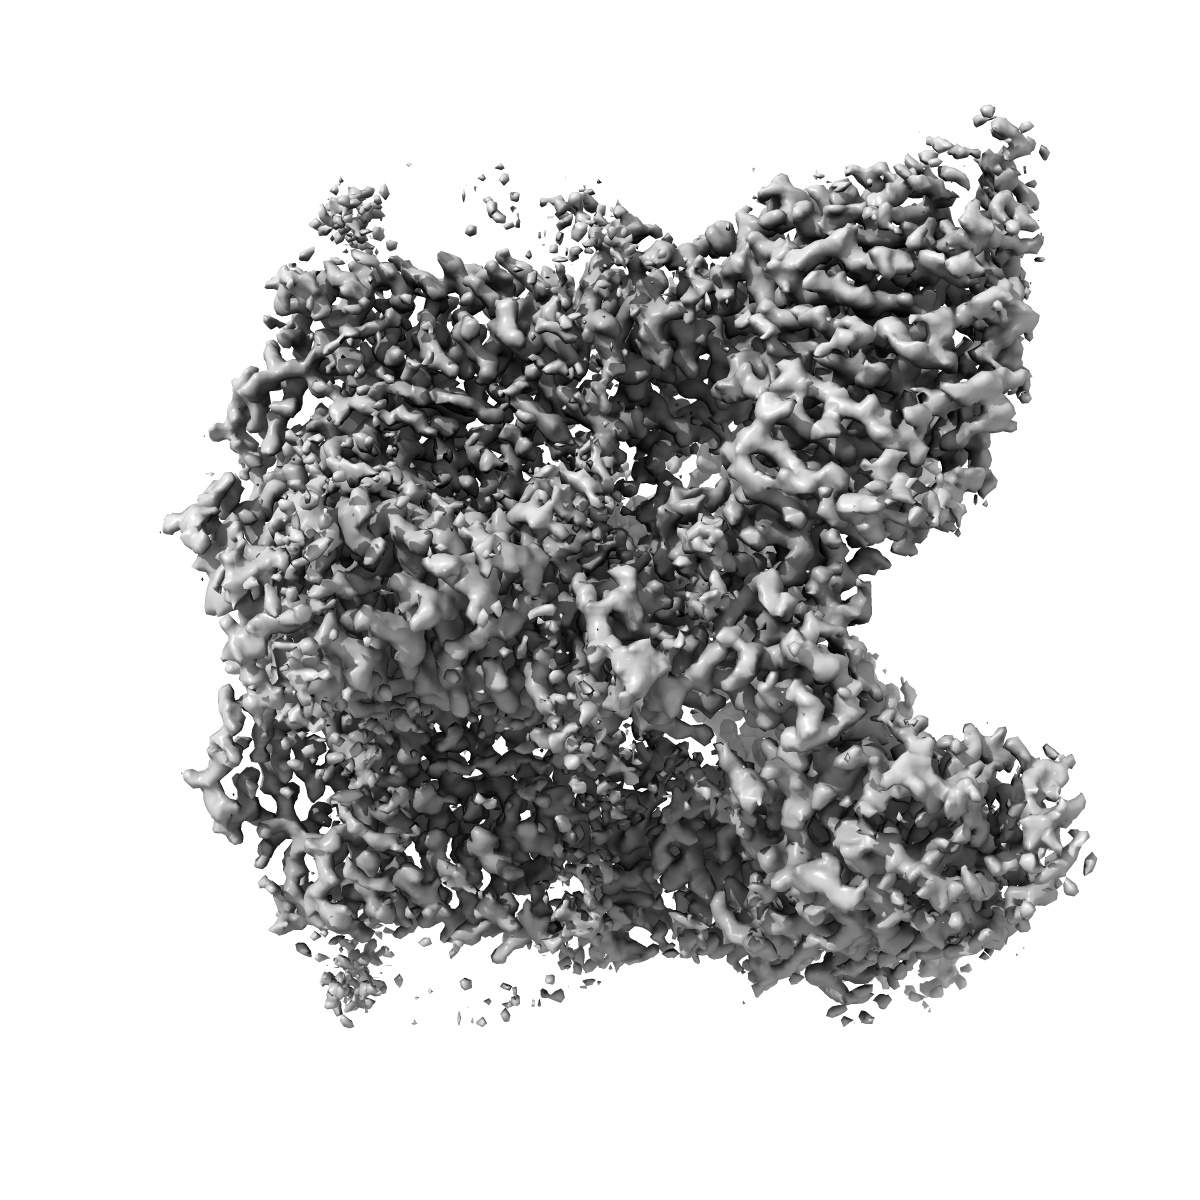

Cryo-EM structure of human TRPV6 in complex with inhibitor econazole

Structural mechanisms of TRPV6 inhibition by ruthenium red and econazole.

Neuberger A , Nadezhdin KD , Sobolevsky AI

(2021) Nat Commun , 12 , 6284 - 6284